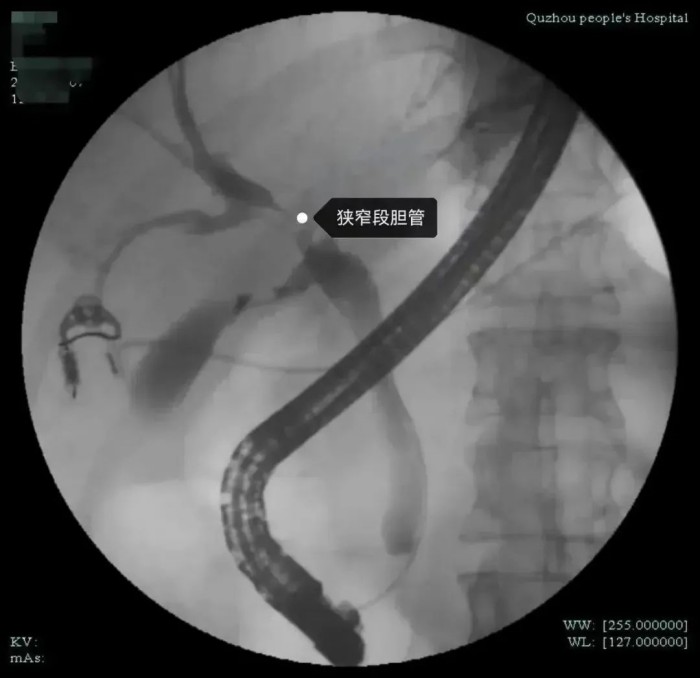

市人民醫(yī)院腫瘤放療科姜忠于主任醫(yī)師認(rèn)為目前不能排除腫瘤可能,需要做進(jìn)一步檢查,以明確診斷。同時(shí)肝膽外科袁磊博士和沈紅波主任醫(yī)師進(jìn)行會診。經(jīng)全面評估分析,醫(yī)生發(fā)現(xiàn)患者肝門部膽管狹窄,腫瘤標(biāo)記物不高,肝功能目前正常,狹窄局部無明顯腫塊,但仍不能排除膽道內(nèi)病變可能,決定對張女士行ERCP(內(nèi)鏡下逆行膽胰管造影術(shù))檢查,同時(shí)在ERCP下行經(jīng)口膽道鏡檢查。

經(jīng)過與張女士及其家屬詳細(xì)溝通后,在麻醉科、內(nèi)鏡中心的全力配合下,沈紅波為張女士實(shí)施了無痛經(jīng)口電子膽道鏡檢查。術(shù)中,沈紅波發(fā)現(xiàn)膽管狹窄處蒼白僵硬,黏膜表面雖然無明顯新生物,但仍不能排除膽管內(nèi)腫瘤的可能性。因此,他在膽道鏡探查的同時(shí)也取活檢和細(xì)胞刷檢,來鑒別是否是腫瘤。很快,術(shù)后活檢結(jié)果出來了,病理切片提示為惡性腫瘤。

沈紅波介紹,我院率先在衢州地區(qū)引進(jìn)了經(jīng)口電子膽道鏡系統(tǒng),該設(shè)備可以進(jìn)入膽胰管內(nèi)進(jìn)行直視下的檢查,有利于早期發(fā)現(xiàn)病灶,精準(zhǔn)取活檢。直視電子膽道鏡的內(nèi)鏡直徑為9Fr(3毫米),可以進(jìn)入肝內(nèi)的3-4級膽管及胰管內(nèi)。既往傳統(tǒng)的十二指腸鏡無法進(jìn)入膽管內(nèi)進(jìn)行直視檢查治療,膽管內(nèi)結(jié)石等病變只能通過透視下的模糊影像辨認(rèn)。以前要想進(jìn)行膽道內(nèi)直視檢查,需借助腹腔鏡或經(jīng)皮經(jīng)肝膽道穿刺建立通道后才能將膽道鏡送入膽管,創(chuàng)傷大。但直視的電子膽道鏡可以通過十二指腸鏡鉗道內(nèi)進(jìn)入到膽管、胰管內(nèi)進(jìn)行直視下觀察病變、取活檢、碎石等治療,能夠早期發(fā)現(xiàn)微小病變,特別是對于膽胰腫瘤的早發(fā)現(xiàn)、早治療具有很高的臨床價(jià)值。